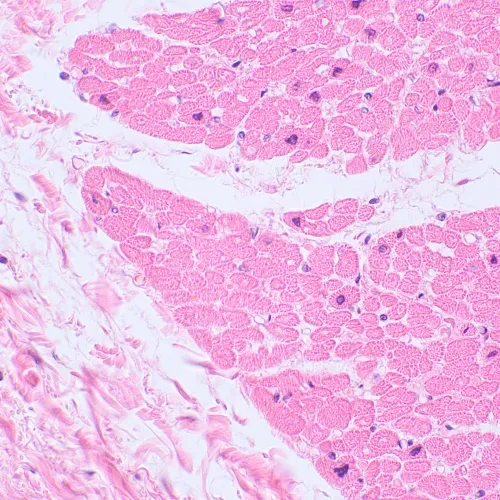

Biologický mikroskop MAGUS Bio 230TL je nezbytným nástrojem v laboratoři hygienické kontroly i v diagnostickém nebo výzkumném centru. Mikroskop má trinokulární hlavu a zdroj procházejícího světla (LED) a je vhodný k pozorování průsvitných a průhledných vzorků. V základní konfiguraci se k pozorování používá technika světlého pole. S dalším příslušenstvím jsou pro další výzkum k dispozici mikroskopické techniky, jako je tmavé pole, polarizované světlo a fázový kontrast.

Možnosti použití laboratorní/lékařská

Metody pozorování světlé pole